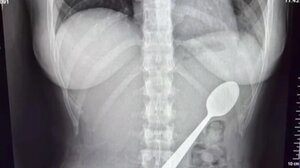

Εσπευσμένα στο ΠΑΓΝΗ 25χρονη που κατάπιε... κουτάλι ΚΡΗΤΗ 21.10.2025Εσπευσμένα στο ΠΑΓΝΗ 25χρονη που κατάπιε... κουτάλι

Επέμβαση στην 25χρονη που κατάπιε κουτάλι - Αφαιρέθηκε από το σώμα της ΚΡΗΤΗ 22.10.2025Επέμβαση στην 25χρονη που κατάπιε κουτάλι - Αφαιρέθηκε από το σώμα της